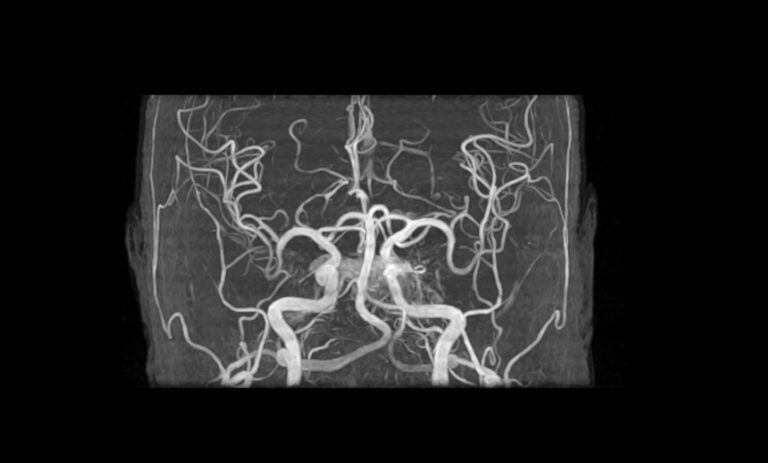

脳の断面画像を写し出すことで、脳卒中(脳出血、脳梗塞、くも膜下出血など)や動脈瘤、脳腫瘍などの早期発見に役立ちます。

脳神経外科では、脳や脊髄、神経などの病気の診断・治療を行います。臨床経験豊富な脳神経外科医が脳疾患の発症リスクを的確に見極め、迅速かつ適切な治療へと繋げます。

脳ドックBRAIN CHECKUP